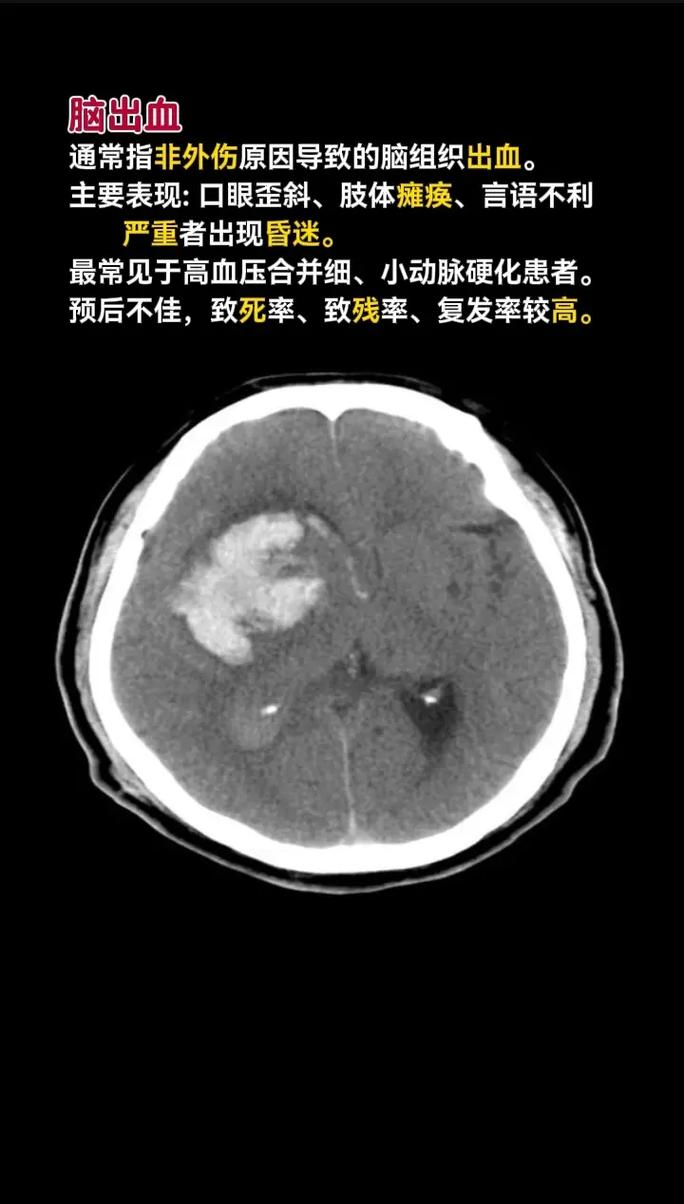

- 脑出血:CT上能非常清晰地显示为高密度(白色)的“血肿”,像一块白色的污渍,这是诊断脑出血最快、最准确的方法。

- 脑梗:在发病超早期(6小时内),CT可能完全正常,或仅有细微变化,发病数小时后,才会看到梗死区域出现低密度(黑色)改变。